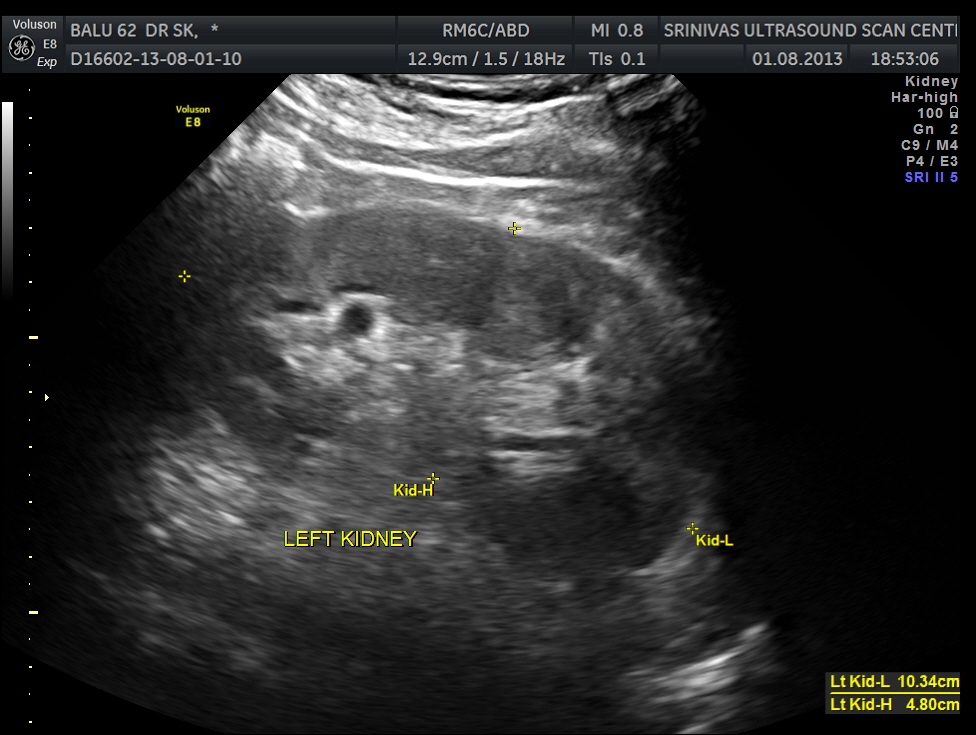

The diagnosis offered was multiple liver secondaries with incidental finding of shrunk right kidney with probable reduced function.